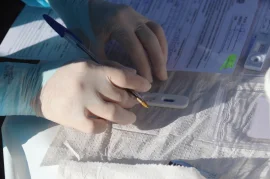

Pesquisadores desenvolvem Teste Popular de COVID-19 que amplia acesso ao diagnóstico

Governo de SP inicia testagem para Covid-19 na rede estadual de ensino

Secretaria de Saúde realiza testagem de Covid-19 no Distrito de Tibiriçá

Mais 238 servidores públicos são testados para Covid-19 em Bauru

Servidores públicos realizam testes de Covid-19, nesta segunda-feira (24)

Servidores públicos de Bauru são testados para Covid-19; mais de 20 positivaram

Prefeitura inicia aplicação de testes de Covid-19 em servidores públicos

Prefeitura de Bauru recebe dois mil testes de Covid da Delegacia da Receita Federal

4ª ação ampliada de diagnóstico da COVID-19 aplica mais de mil testes em Bauru

Ação de diagnóstico da Covid-19 aplicará testes a carros e motos em geral neste sábado (08)

Secretaria de Saúde faz nova ação de testagem para Covid-19 neste sábado (08)

Ação ampliada de diagnostíco para Covid-19 detecta 98 positivos neste sábado (25)

Prefeitura realiza ação ampliada de diagnóstico para a Covid-19 neste sábado (25)

Unesp e municípios do Polo Cuesta firmam convênio para realização de testes de COVID-19

Bauru participa de pesquisa sobre a eficácia de medicamento para a Covid-19

Ação de testagem para Covid-19 detecta 145 casos positivos neste sábado em Bauru

Bauru realiza 1.200 testes para Covid-19 neste sábado (11)

Prefeitura fará ação ampliada para diagnóstico de Covid-19 neste sábado (11)

"Drive Thru" da Covid-19 coleta mais de mil amostras e notifica 56 casos positivos neste sábado (13)

Bauru realiza testagem para Covid-19 em formato drive-thru neste sábado (13)

Secretaria de Saúde treina servidores para aplicação de testes da Covid-19